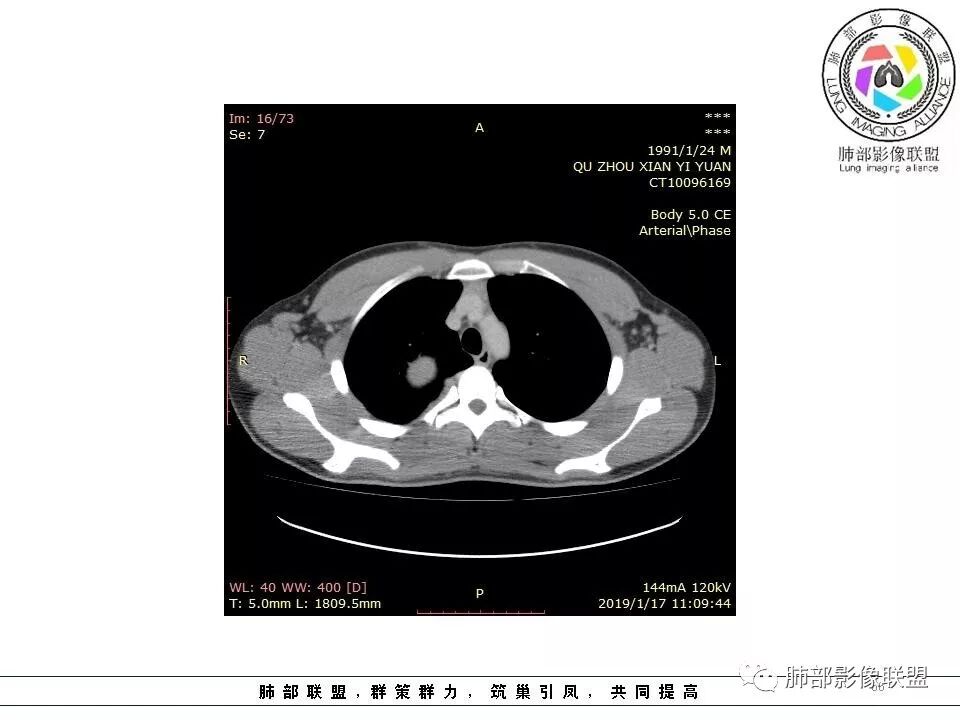

青年男性,间断胸痛;右侧脊柱旁可见一类圆形软组织密度影,密度欠均匀,增强扫描呈轻中度持续强化,邻近肺组织及肺动脉推移,可见肋间动脉供血,部分胸膜下脂肪可见,部分层面似见与右侧椎间孔相连。考虑后纵隔神经源性肿瘤。

青年男性,间断胸痛。右后纵膈脊柱旁软组织占位,形态规则类圆,边缘光整,肺组织受压,D字征,胸膜尾,肋间动脉供血。中度不均匀延迟强化。无支气管进入考虑来源于肺外、肿块与脊柱间未见明显脂肪间隙,考虑来源于胸膜外,考虑神经源性肿瘤,建议穿刺活检。

右肺占位,跨越上叶后段、下叶背,边缘光滑,瘤肺界面清,见肺压缩缘(线样不张`强化),见胸膜尾征,胸膜下脂肪未见明显增厚,肋骨丶脊柱未见侵袭及受压,渐进性丶地图样强化,冠状位似见体循环供血

诊断:SFT(来源壁层胸膜?一般小于20%)

鉴别:神经源性(鞘瘤)、LCD、肉瘤丶孤立性间皮瘤

青年男性,右后上纵隔脊柱旁沟可见团状软组织影,边界清,密度尚均匀,推挤邻近肺组织,胸膜可见掀起,有肺动脉供血,增强轻度蛇皮样强化,纵隔淋巴结未见肿大,邻近骨质未见破坏,胸膜下脂肪间隙消失,考虑SFT孤立性纤维瘤可能性大,鉴别神经鞘瘤,节细胞瘤,建议活检。

右肺上叶纵膈胸膜侧一类圆型肿块,宽基地与胸膜相连,呈D征,边缘光滑,肺部支气管及血管推移,平扫密度均匀,增强后轻度渐近性强化,并可见肋间动脉供血,病变与食管关系模糊,考虑肺外来源,孤立性纤维瘤(有血管穿行),鉴别神经鞘瘤(强化弱,而且椎孔未见扩大),淋巴瘤

青年男性,右侧脊柱旁占位,瘤肺界限清晰,支气管推移,胸膜尾,D字征,胸膜下脂肪影,蛇纹血管,双重供血,延迟强化,定位胸膜,支持sft

边缘光滑,宽基底与胸壁相连,跨叶裂,叶裂稍前推,血管、支气管前移。

浅分叶

外上侧少量胸水

肋间动脉供血,强化尚均匀,逐步强化

胸膜下脂肪间隙?

这个病变看着外面是胸膜模糊的改变,但是血管是从椎间孔过来的,这个胸膜外缘有个间隙存在,个人觉得神经鞘瘤等不能排除。胸膜尾这个征象,外面一层增厚的、延迟第2、3期的局部似乎与肿瘤有间隙,所以不是很踏实。淋巴瘤不太考虑,形态不符,贴在附近软组织梭形改变,有血管进入,当时怀疑淋巴瘤,是上面有个强化的地方不放心。

1.右上胸内脊柱旁类圆形肿块,质地似乎比较坚实,密度稍显不均,但未显示明确的坏死。

如此密度形态的病灶位于肺边缘首先应当想到孤立性纤维瘤,可相邻胸膜未见明显的异常强化和胸膜方向延伸。

3.相邻椎间孔未见扩大,也未见块影延入椎管,易起自于神经根的鞘瘤似乎找不到支持点。

可惜未提供矢状位骨窗图像,如在肋骨内下缘观察到压迹有助于肋间神经的鞘瘤的判断,这是因为二者之间密切的毗邻关系。

4.静脉期轻度不均匀强化,注意不是环形强化,亦未见明确的“AB区”,这点也不支持神经鞘瘤。临床及病灶轻度强化都不支持副节瘤。